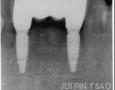

CBCT :

Yes

IMPLANT PLACEMENT:

2 Years